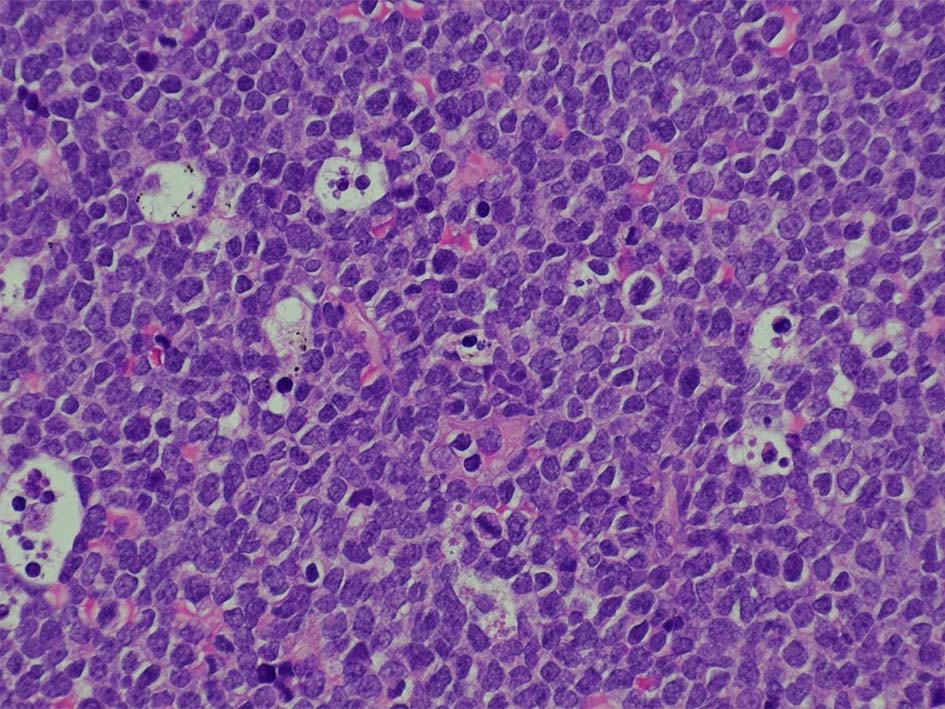

T-lymphoblastic leukaemia/ lymphoma

Tリンパ芽球性白血病/リンパ腫、NOS( WHO5th classification*1)

慣例では、末梢血および骨髄が主要病変部位である場合は白血病(T-ALL), リンパ節、胸腺またはその他の結節外部位が主要病変部位である場合はリンパ腫(T-LBL)という用語を使用する。

Tリンパ芽球性白血病とTリンパ芽球性リンパ腫の区別は、臨床像および骨髄浸潤の程度に基づいて行われる。白血病は、末梢血および/または骨髄に著明な浸潤を認める疾患(通常、骨髄芽球25%以上とみなされる)を指すのに対し、リンパ腫は、胸腺、リンパ節または節外部位への浸潤を含む、組織ベースの腫瘤性病変を指し、末梢血または骨髄への浸潤はないか、あってもごくわずかである*2。 末梢血/骨髄の浸潤と腫瘤性病変の両方がある場合は、有意な区別はない。一般に、両者には生物学的および臨床的に大きな重複があり、WHOの分類スキーム(WHO4th rev Ed 2017)によれば、臨床像の異なる同一疾患とみなされる。

T-ALL/LBL 縦隔腫瘍, 胸水貯留症例

70歳男性 KNS

右肺上葉から前縦隔に90mm大の腫瘤あり. 右胸水貯留を伴う. 右主気管支よりEBUS-TBNAをおこなう.